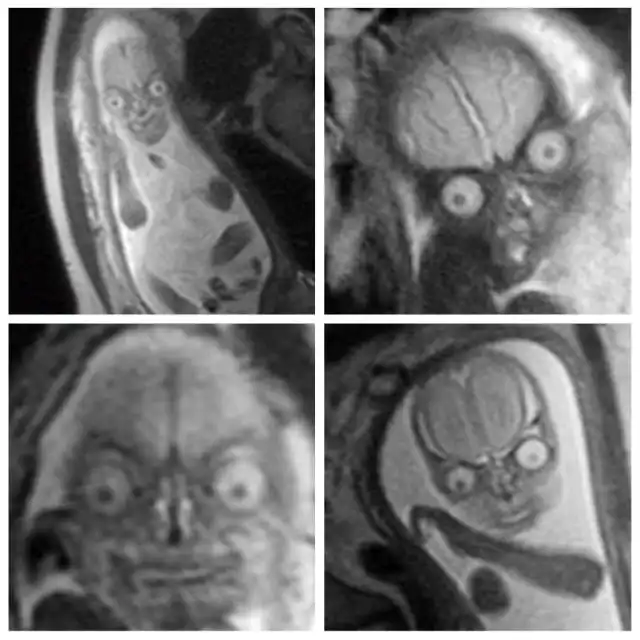

Всегда подмечал в голливудских фильмах такое клише: беременной девушке делают УЗИ, а потом показывают матери и отцу эмбриончик, после чего все начинают умиляться, охать и обниматься, несмотря на то, что на экране по сути ничего не видно. В которой раз можно убедиться в том, что в мелодрамах правды нет. Это подтверждают жуткие МРТ-снимки беременной женщины из реальной жизни. Честно скажу, мне это сегодня приснится. Впечатлительным я бы рекомендовал не смотреть.